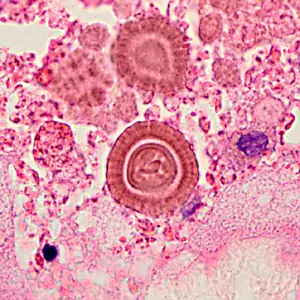

An 83-year-old man presented to a medical institution with shortness of breath and left flank pain that developed during a trip to Mexico shortly beforehand. Magnetic resolution imaging (MRI) revealed an exophytic mass on his left kidney. Approximately 4 months later he underwent surgery and the mass was sent to Pathology for analysis. The pathology report stated foreign elements of unknown etiology observed in perinephritic fat. Gomori-Grocott methenamine silver (GMS) and periodic acid-Schiff (PAS) stains were negative for fungal organisms. Images were captured of the objects of interest and sent to DPDx for consult. Figures A–C show the objects; neither magnification used nor size of the objects was given. What is your diagnosis? Based on what criteria?

Figure A